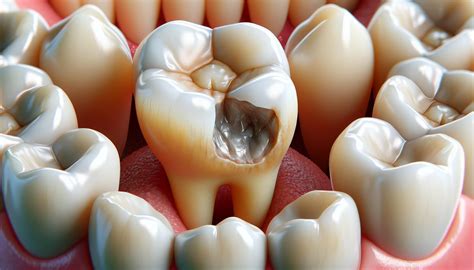

The primary goal of a dental filling is to stop the spread of decay and seal off the affected area to prevent bacteria from re-entering the tooth. When a cavity occurs, the enamel—the hardest substance in the human body—has been compromised. Without treatment, the decay can penetrate deeper into the dentin and, eventually, the tooth’s pulp, leading to infection and severe pain.

• Removal: Carefully removing the decayed portion of the tooth using specialized instruments.

• Cleaning: Thoroughly cleaning the cavity to ensure all bacteria and debris are eradicated.

• Restoration: Filling the void with a restorative material to return the tooth to its original shape and strength.